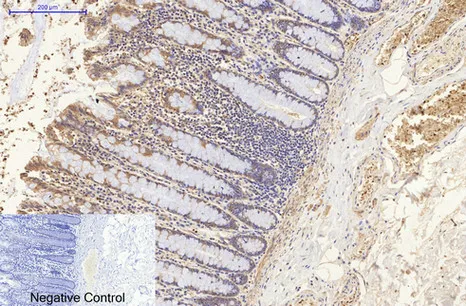

CDX2(14H6)Mouse Monoclonal Antibody

Cat: AMM08595

Size1:50μL Price1:$118

Size2:100μL Price2:$220

Size3:200μL Price3:$380

Application:WB,IF-P,IF-F,ICC/IF,IHC-P

Reactivity:Human,Mouse,Rat

Conjugate:Unconjugated

Optional conjugates: Biotin, FITC (free of charge). See other 26 conjugates.

Gene Name:CDX2